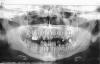

ден Опубликовано 10 октября, 2012 Поделиться Опубликовано 10 октября, 2012 Здравствуйте уважаемые коллеги. Помогите пожалуйста советом.Опыт имплантации небольшой,но есть.Несколько лет работал в клинике самостоятельно, с ортопедом находили общий язык и расхождений в плане лечения не было.Недавно устроился на другую работу. В этой клинике ортопед авторитетный и все с ним считаются.Хотя и сами у него не протезируются, потому как осложнений много и переделок.Но авторитет свой, доктор сохраняет.Так вот к сути вопроса, пришёл пациент 28 лет.Говорит что у него было тяжёлое финансовое положение, в течении нескольких лет. Теперь трудности позади и на новой должности он должен улыбаться и быть красивым.Денежный вопрос его интересует, но не особо.Заболеваний нет.Правда навыки гигиены "хромают".Есть несколько свищевых ходов. Так же отмечается хронический пародонтит с явлениями резорбции костной ткани во фронтальном отделе нижней челюсти. Вот что имеем.Ничего не беспокоит,кроме эстетики. Это тот план который я предложил.После удаления где то потребуется внесение в лунку остеотропа. После удаления всех зубов можно одеть временно съёмный протез. Сам я не протезирую, поэтому обратился к ортопеду,он мой план раскритиковал и предложил свой Мотивируя тем что для удаления показаний нет,и всё что можно "спасти" надо "спасать". Депульпировать и покрывать коронками. Причём мой довод о том что мы удаляем подросткам здоровые премоляры для нормализации прикуса не возимели действие.И тот же парадонтит, подвижность 2 степени и гноетечение, не остудил его академический пыл.Подскажите пожалуйста, как бы Вы поступили в данной ситуации? Хочется чтоб "не навреди"... Ссылка на комментарий

doctore Опубликовано 10 октября, 2012 Поделиться Опубликовано 10 октября, 2012 Нужно смотреть модели,фотографии и данные кт.Ваш план - имеет место быть-самый простой вариант.Мне кажется,что зубоальвеолярное выдвижение 16 не позволит его импользовать .Так же как и то, что отсутствие феррула(на мой взгляд)на 22 и 23 не дает возможности их сохранения.Кроме как с использованием техники удлинения клинической коронки.Отсутствие 12 и мезиализация 13 -никаких шансов для создания эстетической реставрации в этой области не оставляют.Верх, по моему мнению, обоснованно идет на вынос.Вопрос по 33-43- открыт. 1 Ссылка на комментарий

Bier Опубликовано 10 октября, 2012 Поделиться Опубликовано 10 октября, 2012 мне категорически не нравятся оба плана лечения. Ну план вашего ортопеда даже обсуждать не хочу, он мягко говоря странный.Теперь про ваш план:верх - согласен с тотальным удалением (но не сразу) не нравится:1. расположение имплантатов (ставить 2 имплантата в резцы нет никакого смысла, на нижней челюсти даже вредно. Я бы вообще очень задумался над тем, нужны ли вообще имплантаты в резцах (внизу точно не нужны), а наверху максимум 1.2. Вы собираетесь в лунки имплантировать? У пациента 13 зуб мезиализирован. Имплантат в этой позиции нам не нужен. При моделировке коронок он окажется между зубов. 47з - вы специально выбрали место с самой большой гранулемой? ))3. Ношение съемных протезов с опорой на слизистую на мой взгляд недопустимо вообще в такой ситуации. Надо искать способы обойтись без них. не удалять сразу все зубы, а оставить часть зубов для фиксации протеза, установить часть имплантатов, после их приживления удалить оставшиеся зубы и доимплантироваться. На нижней челюсти фронтальная группа не выглядит криминальной. Полечите пародонтит, какие проблемы? И гноетечение пройдет и зубы еще постоят. 2 Ссылка на комментарий